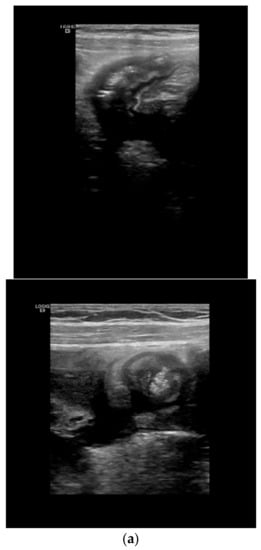

Depending of the CD phenotype, different ultrasonographic characteristics can be identified. The presence of ulcers can be visualized as depressions in the mucosal layer. Strictures are characterized by wall thickening with a narrowed lumen, with or without a dilatation of the proximal loop (pre-stenotic dilatation) (see Figure 5). The fistulae are seen as hypoechoic peri-intestinal areas with diameter < 2 cm with or without internal gaseous artifacts. Abdominal abscesses are seen as hypo-anechoic lesions containing fluid and gaseous artifacts, posterior enhancement, irregular margins sometimes within hypertrophic mesentery, without vascular signals at color Doppler (see Figure 6). An inflammatory mass is seen as an irregular hypoechogenic lesion, with vascular signals at color Doppler.

Figure 5.

Detection of complications: stricture with pre-stenotic dilation: Strictures are characterized by a wall thickening with a narrowed lumen, with or without a dilatation of the proximal loop (pre-stenotic dilatation).

Figure 6.

Detection of complications: fistulae and abscesses: (a) The fistulae are seen as hypoechoic peri-intestinal areas with a diameter <2 cm with or without internal gaseous artifacts. (b) Abdominal abscesses are seen as hypo-anechoic lesions containing fluid and gaseous artifacts, posterior enhancement, irregular margins sometimes within fibro-fatty proliferation, without vascular signals in color Doppler.